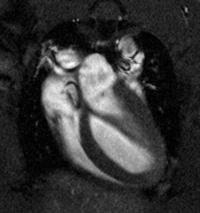

Pictured (Left): Long Axis CINE Image

of a Rodent Heart acquired

at UHF (9.4T) MRI Scanner (SBIC)